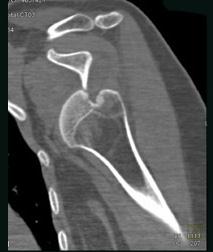

问题 男,18岁,肩部外伤,疼痛、活动受限,结合图像,最可能的诊断是 ( )

选项 A、肩锁关节脱位 B、肩关节未见脱位 C、肩关节喙突下脱位 D、肩关节锁骨下脱位 E、肩关节盂下脱位

答案 E